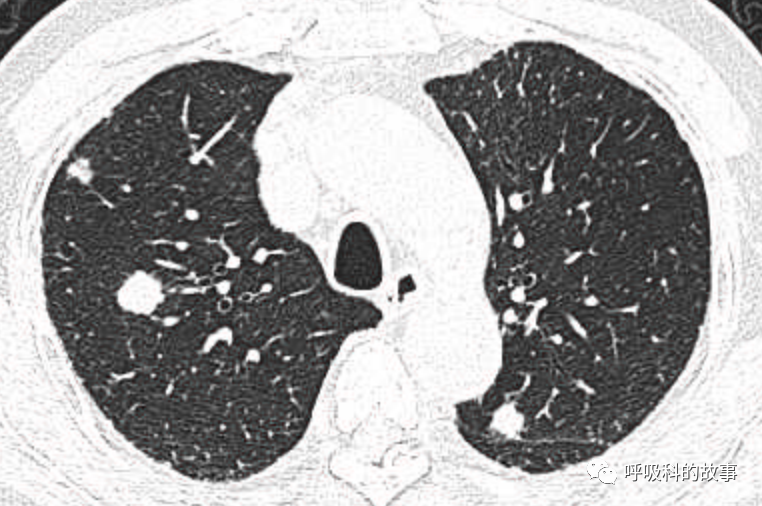

1个月前,我们收治了一个80多岁的男性患者,两肺多发结节和肿块,锁骨上淋巴结也触及肿大,在接诊时我们就预感不妙,患者很可能是患上了肺癌。后来经过穿刺后明确为大细胞神经内分泌癌,CT如下。

图1-11:该患者各个角度的影像图像

(上下滑动查看全部图片)